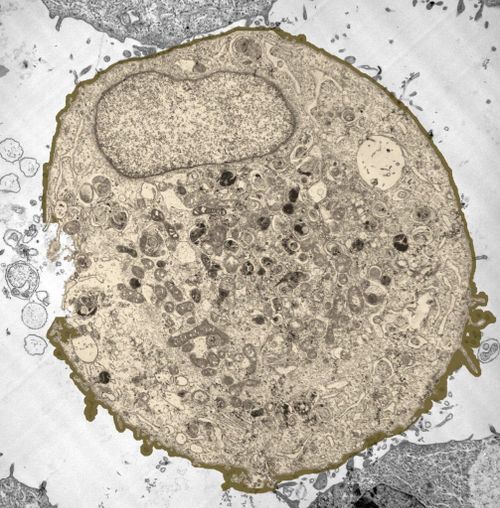

Заглавно изображение: Животинска клетка под микроскоп.